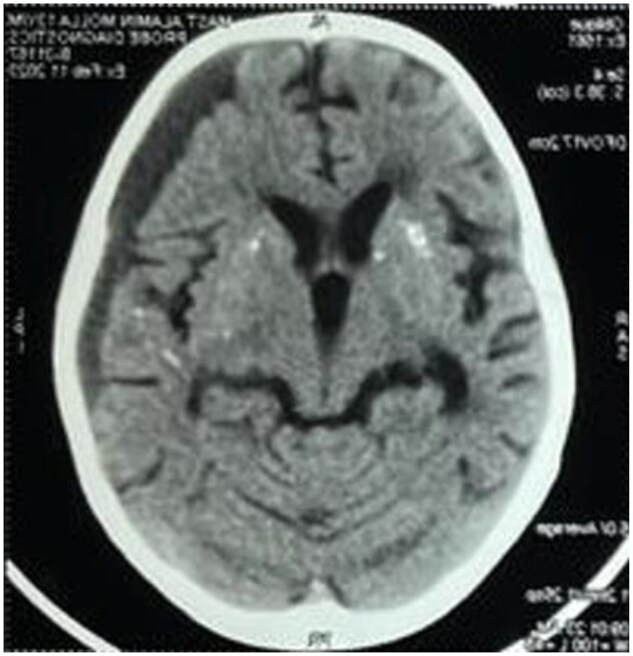

Results: We describe four cases of C1Q monogenic lupus identified by whole exome sequencing. All patients exhibited mucocutaneous involvement, discoid lupus erythematosus, inflammatory polyarthritis, normal serum complements C3 and C4, coarse-speckled Antinuclear antibody positivity and antibodies to ribonucleoprotein. Unique features identified include brain parenchymal calcification in one case, chronic subdural haemorrhage in two cases, infection complicated by macrophage activation syndrome in two cases and myositis in one case. Patients were treated with conventional immunosuppressive therapy (glucocorticoids, mycophenolate, cyclophosphamide) and Fresh Frozen Plasma. Our findings were compared with existing literature on C1q deficiency, noting frequent presentations with mucocutaneous and musculoskeletal manifestations, normal C3 and C4 levels and absence of anti-dsDNA antibodies.